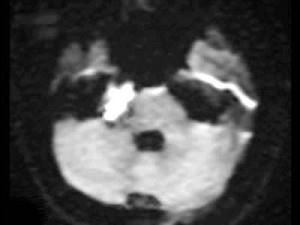

男,42岁,右侧听力下降,MRI检查如图,最可能的诊断为()A.表皮样囊肿B.听神经瘤C.三叉神经瘤D.脑膜瘤E.脑梗死

问题 男,42岁,右侧听力下降,MRI检查如图,最可能的诊断为()

选项 A.表皮样囊肿 B.听神经瘤 C.三叉神经瘤 D.脑膜瘤 E.脑梗死

答案 A